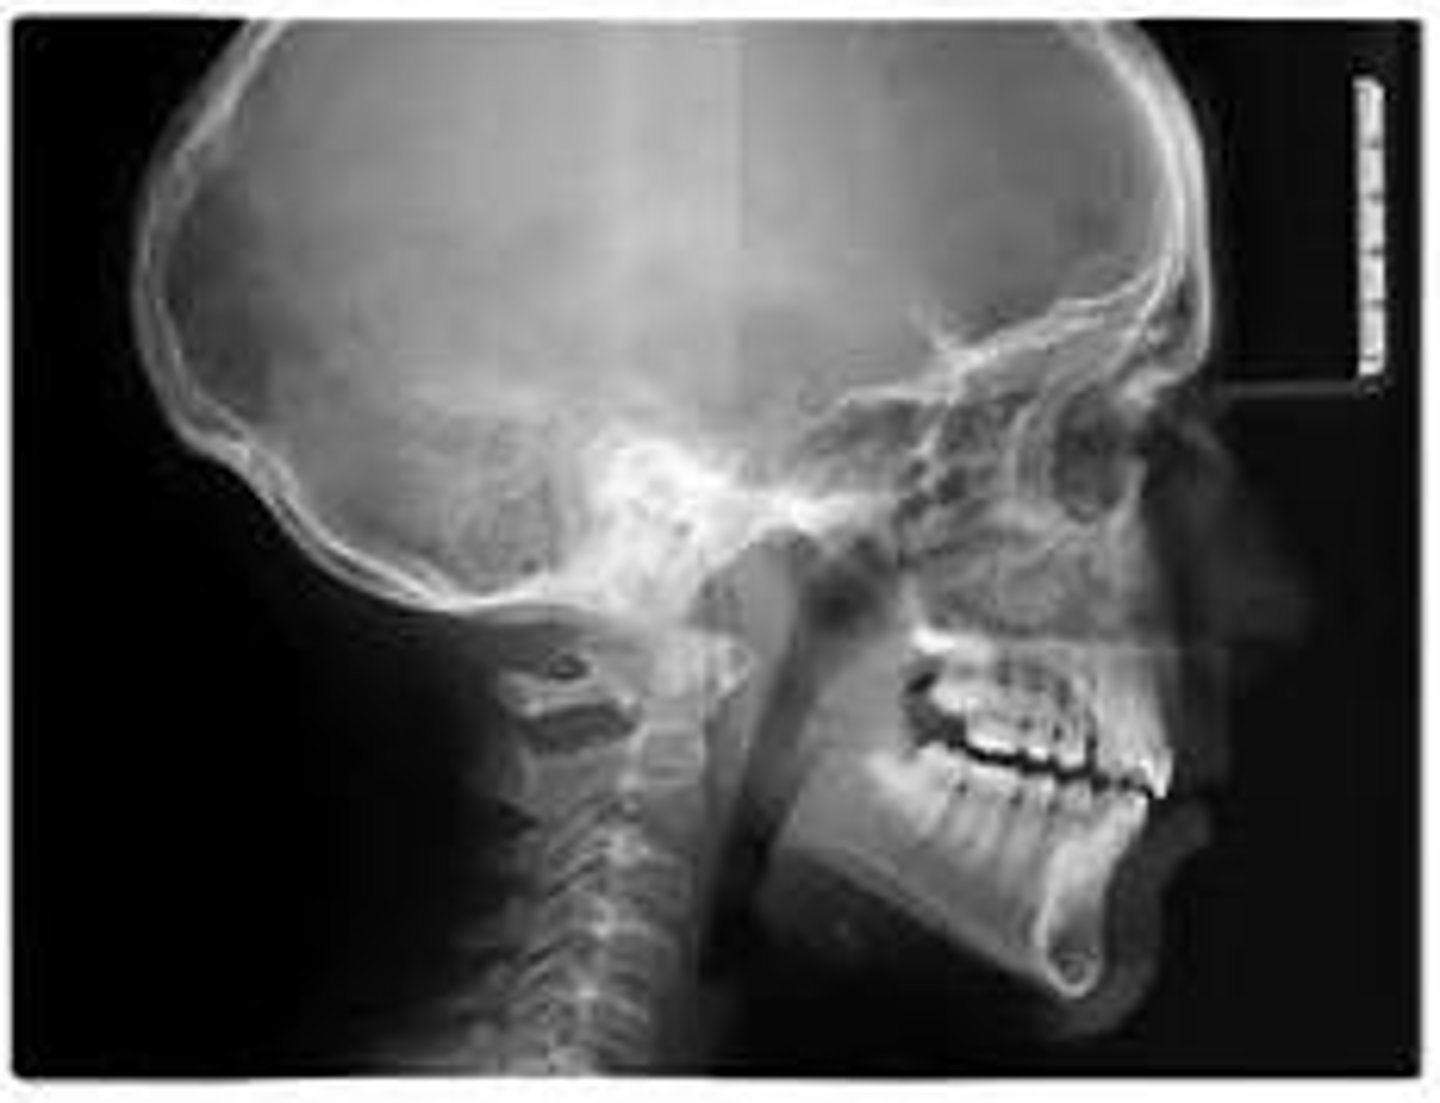

Cephalometric (ceph)

what type of x-ray is this?

what does a cephalometric x-ray show?

a lateral side profile of the entire skull & jaw

what is the primary purpose of a cephalometric x-ray?

FOR ORTHODONTICS/ORAL SURGERY (measuring the relationship between the teeth, jaw & facial profile)

what are the other purposes of a cephalometric x-ray?

- treatment planning

- monitoring facial growth & development